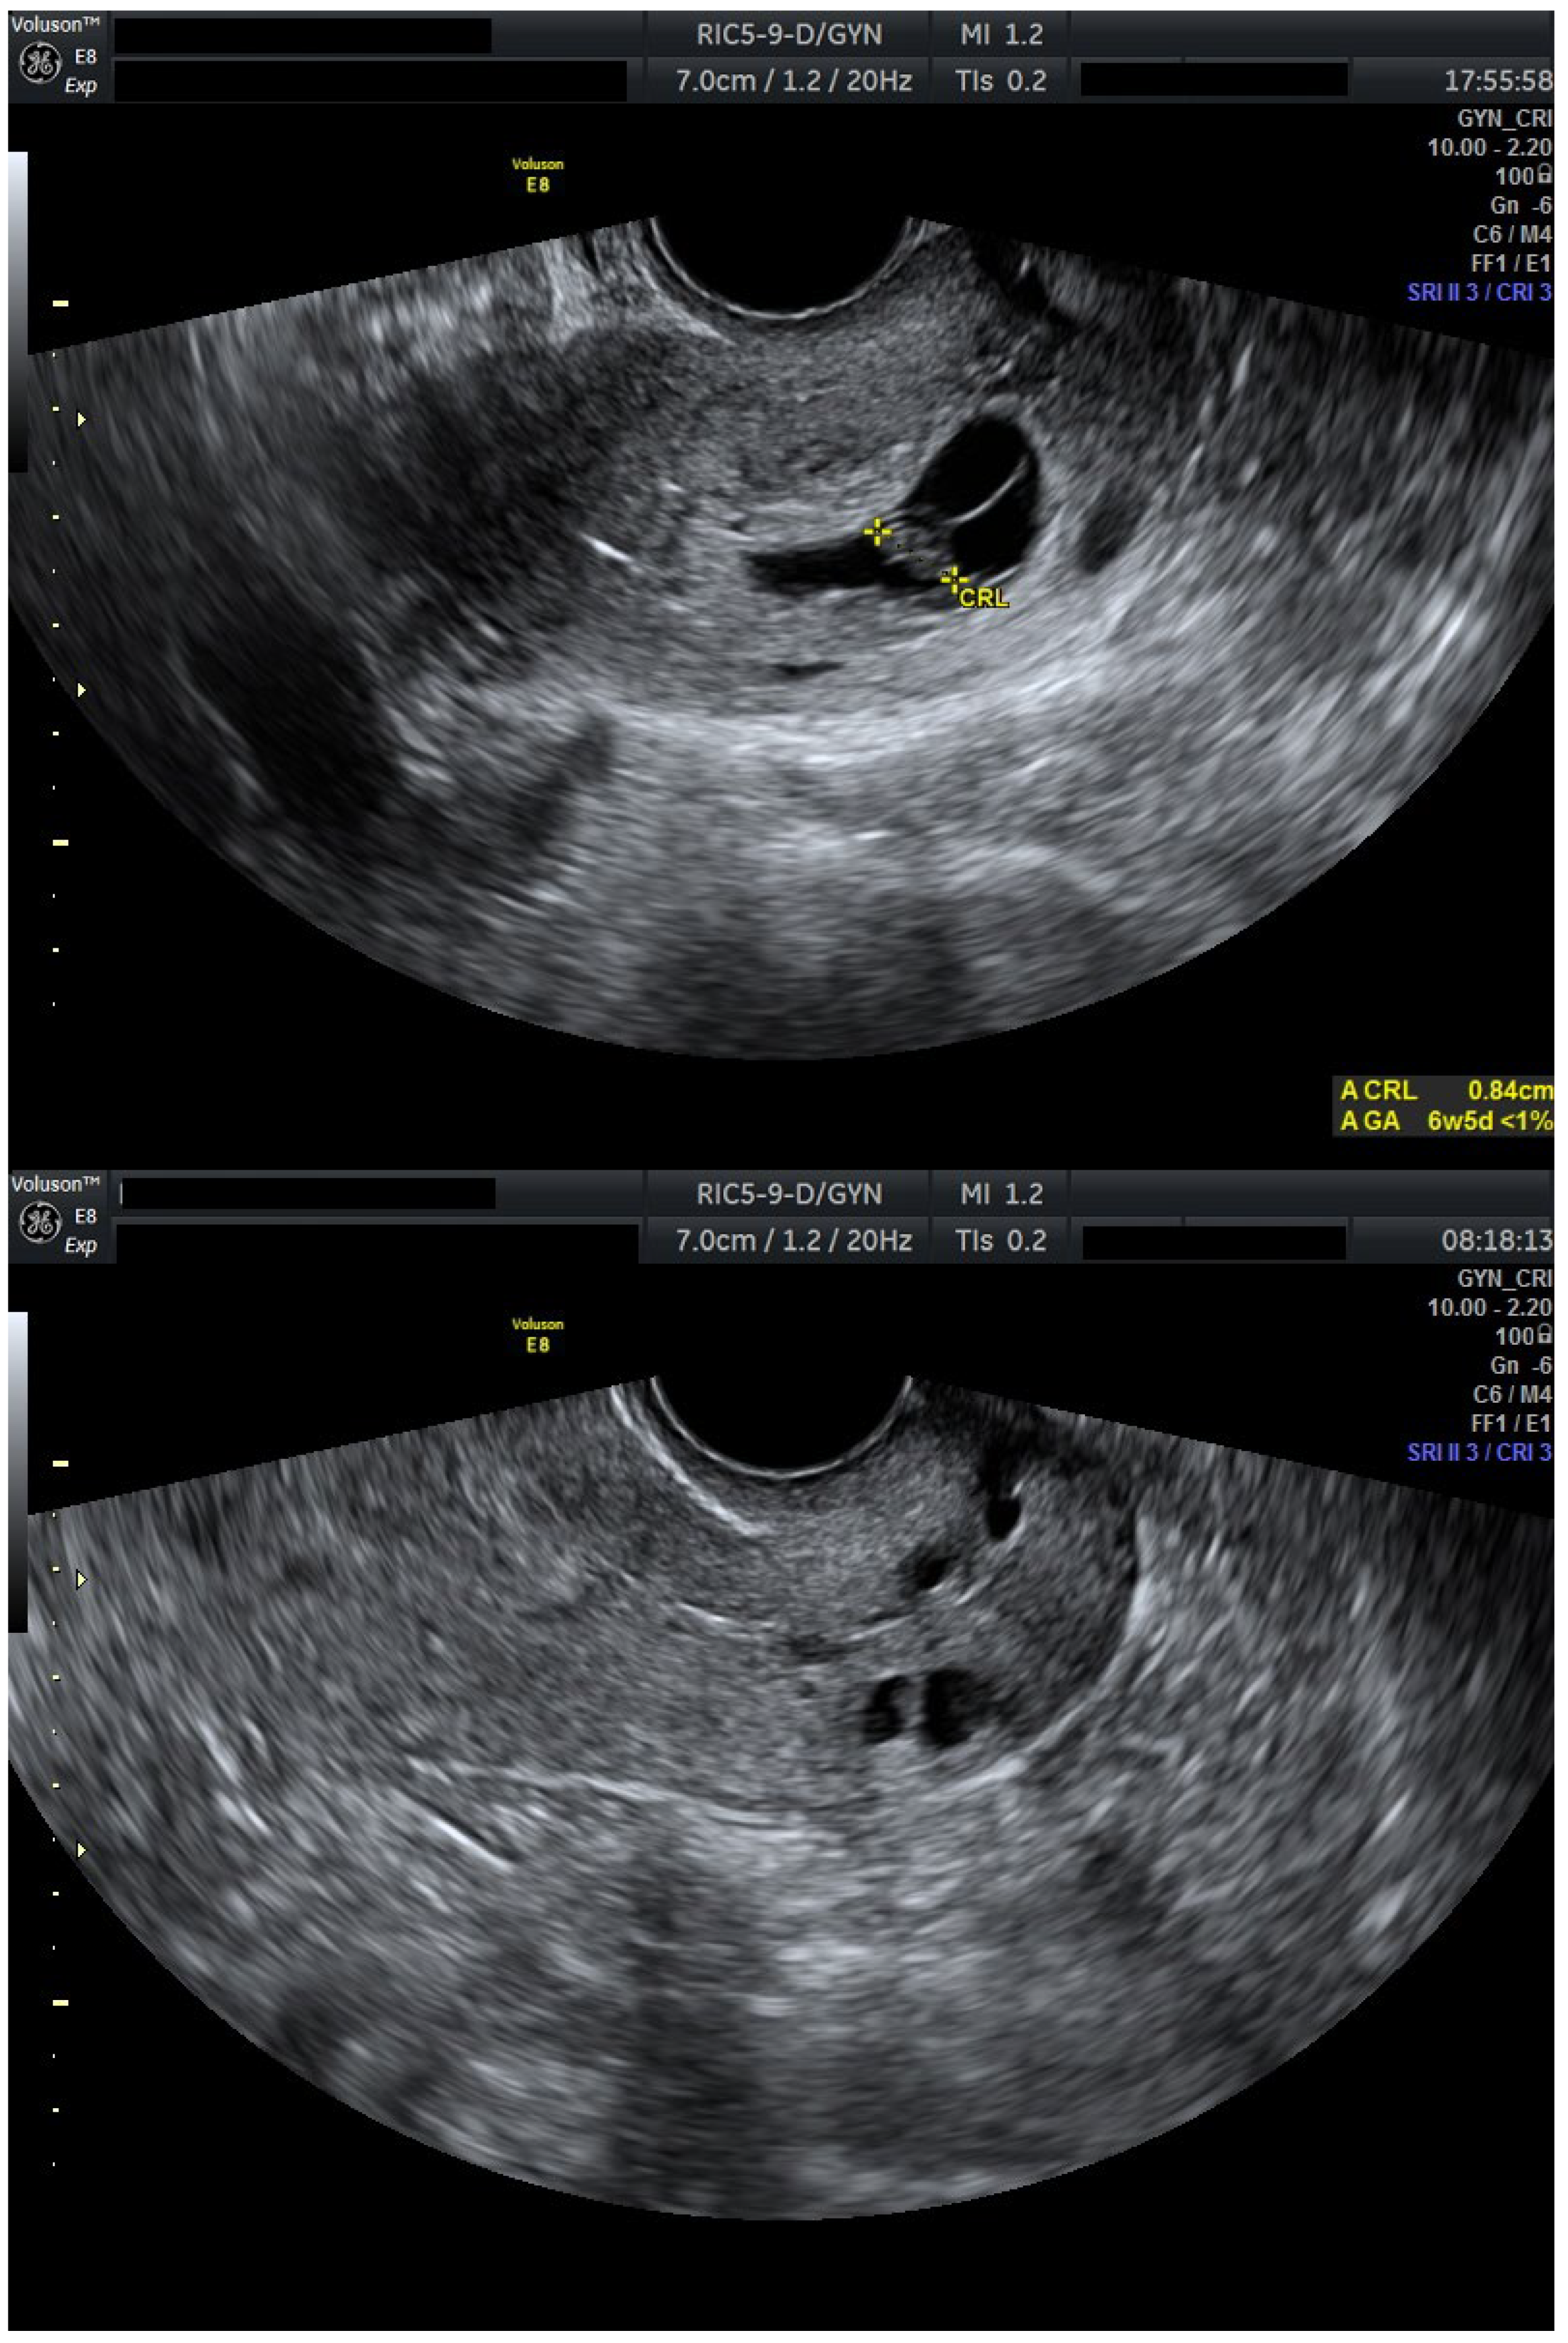

3. Personal Experience

We present a personal case from our tertiary center in western Romania as an example of applicable findings from this review. A 32-year-old woman presented to the Municipal Clinical Emergency Hospital of Timișoara with first-trimester vaginal bleeding. Transvaginal ultrasound revealed a viable intrauterine gestation with a seven-week-old embryo with positive cardiac activity, as well as a simultaneous viable CP, confirming the diagnosis of HCP (Figure 1).

Figure 1.

Ultrasound evaluation at diagnosis with viable heterotopic embryos (Day 0). Combined ultrasound of both gestational sacs. Transvaginal ultrasound evaluation: sagittal view through the uterus and cervical canal. FHR present in both embryos. Patient information is anonymized.